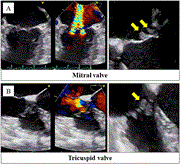

Postoperative anticoagulation management using subcutaneous unfractionated heparin for a patient with nonbacterial thrombotic endocarditis: a case report

Hiroki Mine and others

Journal of Surgical Case Reports, Volume 2024, Issue 4, April 2024, rjae215, https://doi.org/10.1093/jscr/rjae215